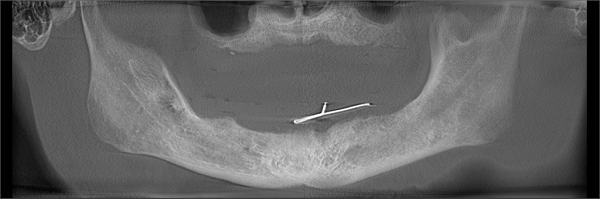

所以张院长先给杨爷爷做了一套详细的检查,杨爷爷身体硬朗,牙槽骨健康程度符合种植半口牙的条件,于是他采用了德韩口腔特有的“德国Weimar亲骨种植术”。

4月23日,张院长为杨爷爷种下了人工牙根,就等4个月后,等牙根长牢了,再为杨爷爷安装种植牙。